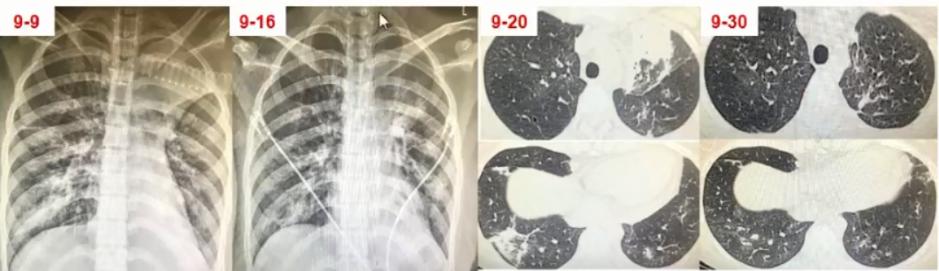

图2 影像表现以多发肺结节合并晕征,类似于真菌感染

图3 双肺弥漫性小结节为主,中下肺布满粟粒样小结节,部分融合成片状